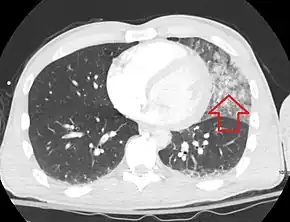

Computed tomography

Computed tomography (CT scanning) is a more sensitive test for pulmonary contusion,[3][32] and it can identify abdominal, chest, or other injuries that accompany the contusion.[37] In one study, chest X-ray detected pulmonary contusions in 16.3% of people with serious blunt trauma, while CT detected them in 31.2% of the same people.[45] Unlike X-ray, CT scanning can detect the contusion almost immediately after the injury.[42] However, in both X-ray and CT a contusion may become more visible over the first 24–48 hours after trauma as bleeding and edema into lung tissues progress.[46] CT scanning also helps determine the size of a contusion, which is useful in determining whether a patient needs mechanical ventilation; a larger volume of contused lung on CT scan is associated with an increased likelihood that ventilation will be needed.[42] CT scans also help differentiate between contusion and pulmonary hematoma, which may be difficult to tell apart otherwise.[47] However, pulmonary contusions that are visible on CT but not chest X-ray are usually not severe enough to affect outcome or treatment.[36]